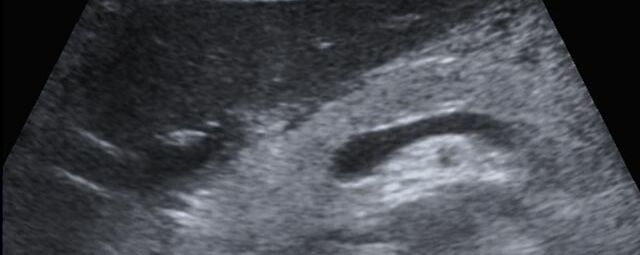

Die Sonographie ist ein bildgebendes Verfahren in der medizinischen Diagnostik, das mit Ultraschallwellen arbeitet. Ultraschall ist Schall mit einer Frequenz oberhalb der menschlichen Hörgrenze. Im medizinischen Bereich werden je nach Körperregion Ultraschallwellen in einem Frequenzbereich von ca. 3,5 – 18 Mhz verwendet. Die körpernahe Ultraschallsonde sendet durch einen piezoelektrischen Effekt kurze Schallwellenimpulse in den Körper. Ultraschall-Gel stellt den Kontakt zwischen Sonde und Körper her. Je nach Gewebeart werden diese Schallwellen im Körper unterschiedlich stark reflektiert. Anhand des zurückgesendeten Schallmusters kann das Ultraschallgerät Schnittbilder berechnen, auf denen die Organe des Körpers nach krankhaften Veränderungen untersucht werden können.